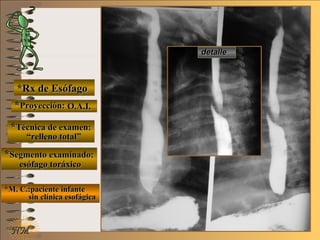

*Rx de Esófago*Rx de Esófago

**Proyección:Proyección:

**Técnica de examen:Técnica de examen:

**Segmento examinado:Segmento examinado:

*M. C.:paciente infante*M. C.:paciente infante

sin clínica esofágicasin clínica esofágica

detalledetalle

O.A.I.O.A.I.

““relleno total”relleno total”

esófago toráxicoesófago toráxico

A-A-El examen es normal o patológico?El examen es normal o patológico?

Examen patológico de esófago toráxico con relle-Examen patológico de esófago toráxico con relle-

no total y en proyecciones O.A.I.no total y en proyecciones O.A.I.

B-B-La patología es congénita o adquirida?La patología es congénita o adquirida?

Patología congénita; verPatología congénita; ver

Clasificación General UNTClasificación General UNT

C-C-Puede describir la o las imágenes patológicas?Puede describir la o las imágenes patológicas?

**OpciónOpción

Se identifica un trayecto en “doble tinte” que alte-Se identifica un trayecto en “doble tinte” que alte-

ra la densidad y homogeneidad de la columnara la densidad y homogeneidad de la columna

baritada, que va de abajo arriba, de izquierda abaritada, que va de abajo arriba, de izquierda a

derecha en el frente y en el perfil se proyecta enderecha en el frente y en el perfil se proyecta en

el borde posterior de esófago superior.el borde posterior de esófago superior.

Corresponde al “nacimiento” anómalo de la arte-Corresponde al “nacimiento” anómalo de la arte-

ria subclavia derecha, en el borde izquierdo deria subclavia derecha, en el borde izquierdo de

la aorta, se conoce como “disfagia lusoria”la aorta, se conoce como “disfagia lusoria”